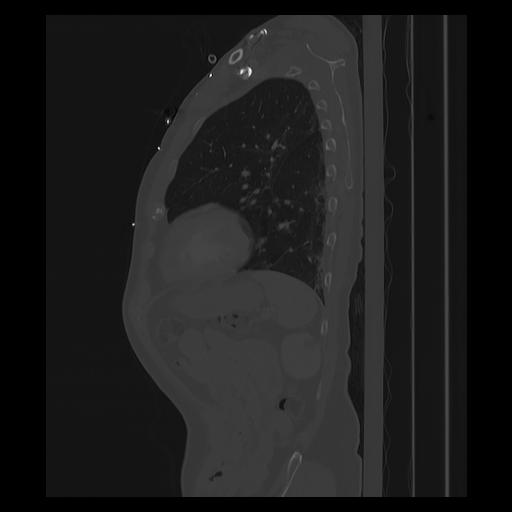

33 PULMON,CE,Sagittal,3.000,PULMON,Sagittal,